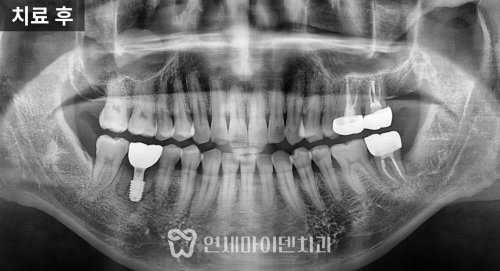

최종 치료 결과

최종적으로 위아래 치아는 가지런하게 배열되었고

왜소치 부위도 라미네이트 보철

심미성과 기능이 보완되었습니다.

치료 기간은 약 2년이 소요되었고,

파노라마 방사선에서도 치근 흡수나 잇몸 손상 없이

안정적으로 마무리되었습니다.